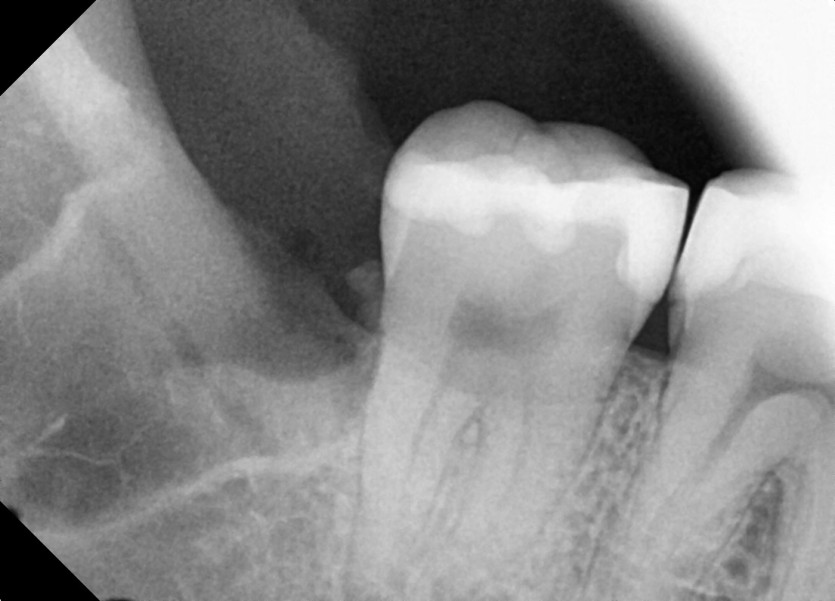

#38,48 사랑니 발치

구강 외과 전문의가 당일발치했습니다.